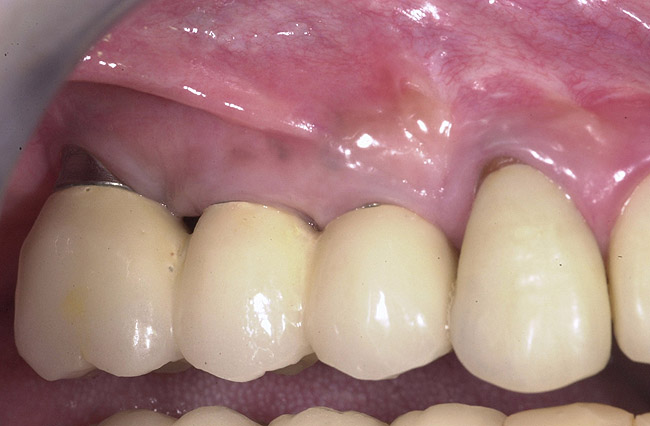

Figure 9  Final implant-supported restoration.

Figure 9